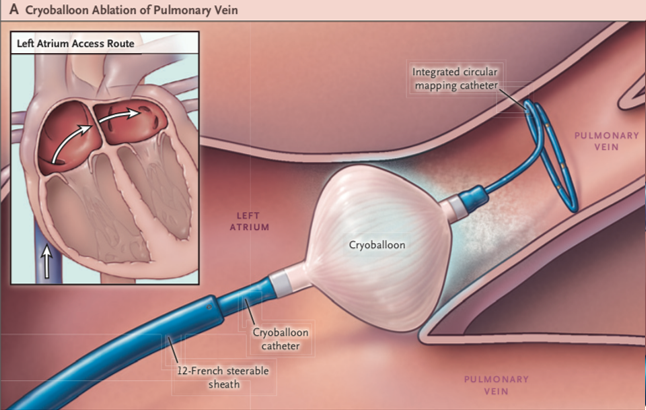

高周波アブレーションという高周波電流を通電して焼灼する方法以外に、心房細動の初回症例や発作性上室頻拍の一部(房室結節リエントリー性頻拍)に対する治療として、冷凍アブレーション(クライオアブレーション)を積極的に取り入れ、より安全な治療を心がけています。

さらに、昨年9月より保険適応となり使用可能になったパルスフィールドアブレーションは従来の熱アブレーション(高周波アブレーション:高周波電流で組織に熱を発生させ焼灼する、クライオアブレーション:冷却されたバルーンを組織に押し当て冷凍凝固を行う)とは異なるエネルギー(パルス電圧)にて心房細動の原因となる心房筋を選択的に焼灼する新しい治療法です。パルスフィールドアブレーションは心筋細胞特異的に焼灼を行うことが可能であるため肺静脈、食道や横隔神経などの周辺組織に関する合併症の発生リスクを低減することが期待されています。パルスフィールドアブレーションは当院でも本年2月より使用可能となりました。今後はそれぞれの患者さんの病態に応じた治療の選択肢が増え、より患者さんに適した治療を選択できるようになりました。

Cryoballoon or Radiofrequency Ablation for Paroxysmal Atrial Fibrillation.

N Engl J Med. 2016;374(23):2235-45. より引用